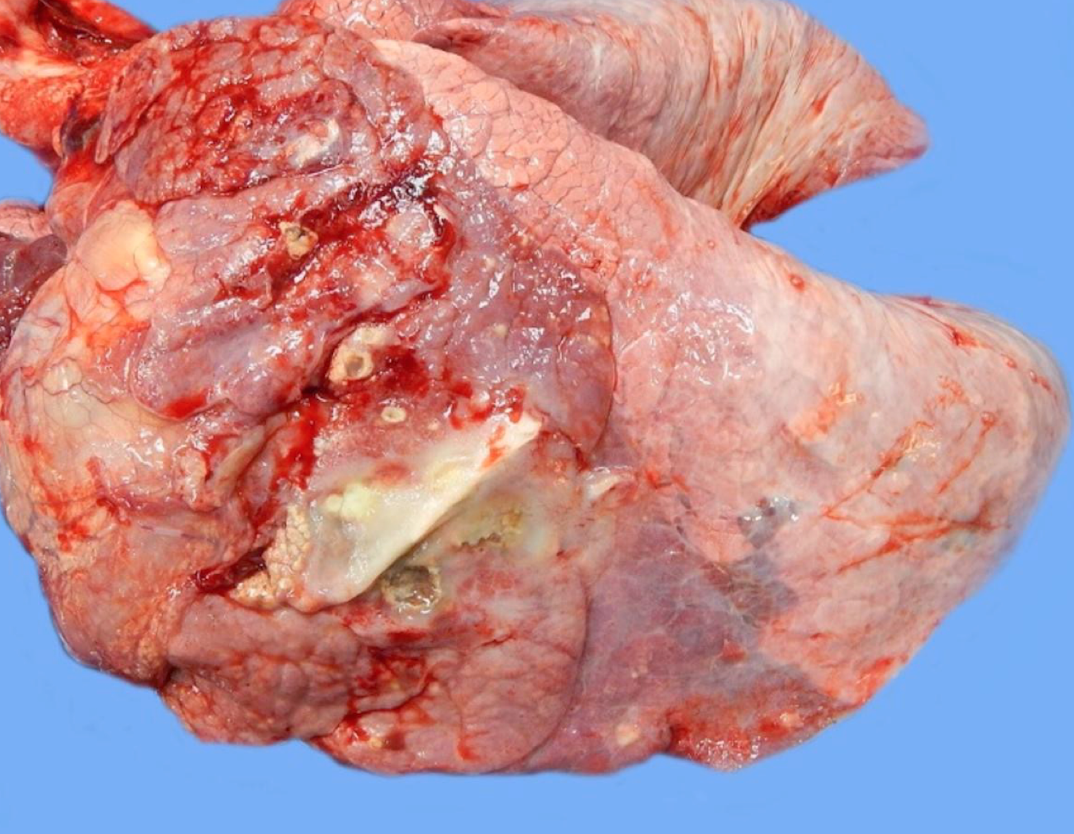

The right cranial lung lobe is completely twisted (360 degrees) around its hilus. The affected lobe is diffusely swollen, dark red, and firm.

Torsion leads to compression of the pulmonary veins. The more muscular arteries typically allow for blood to continue to flow into the affected lung lobe, which then becomes congested as blood pools in the vasculature behind the obstructed vein(s). The retained blood becomes depleted of oxygen, and the cells may undergo ischemia and necrosis (infarct).

Fluid within the thoracic cavity may lead to lung lobe torsion. The air in the lungs makes them buoyant, and so lung lobes in fluid may float and rotate around their blood supply.

Other associated factors are trauma, pulmonary or pleural space disease (including neoplasia), or prior thoracic surgery. Many cases of lung lobe torsion are of unknown cause. Large, deep-chested dogs are predisposed.